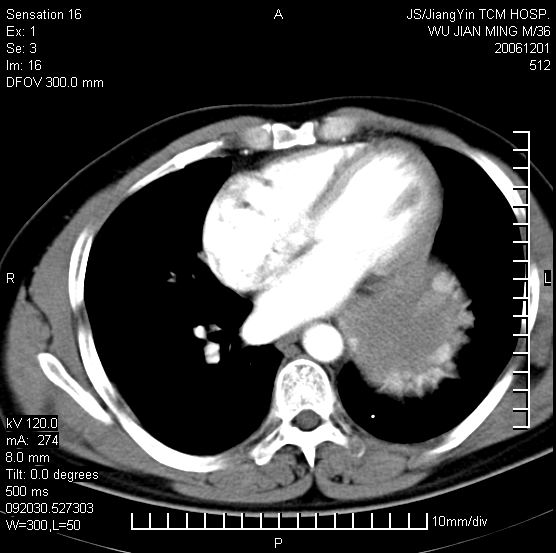

以下是引用dyqct在2006-12-1 21:17:00的发言:[br]左心缘旁及后肋膈窦区见巨大椭圆形混杂密度肿块,周围见大小不等斑片状钙化,内部无强化,周围包膜轻度强化,心脏明显受压变形,即明显占位效应,肿块广基与心包、膈相连。肝、脾内、肝门见多数小结节状钙化影。[br]考虑:1、左心缘旁及后肋膈窦区慢性包裹性胸膜炎(结核性);[br] 2、肝、脾及肝门淋巴结核已钙化。[br]

以下是引用zrs在2006-12-2 17:28:00的发言:[br]肺内、肝脾内虽有钙化,但不支持结核性胸胸膜炎包裹,而支持寄生虫感染![br][br]